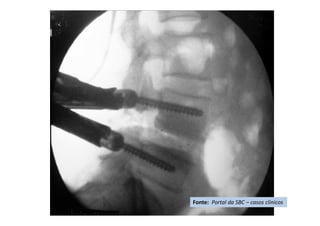

Apresentação de Casos Clínicos

• Escoliose Idiopática do Adolescente

• Resumo do caso: Escoliose idiopática do adolescente tratada

cirurgicamente com artrodese da coluna T4L1 com parafusos

pediculares.

• Paciente (dados): feminino, 13+2 anos, Risser 3, menarca há

9 meses.

• História: Deformidade da coluna percebida pela mãe há 3

meses. Nega tratamento prévio. Nega demais doenças ou uso

de medicações.

• Diagnóstico(s): Escoliose idiopática do adolescente, Lenke

1B-. Tratamento(s): Artrodese da coluna por via posterior T4-

L1 com parafusos pediculares.

• Seguimento ("Follow up"): Seguimento de 2

anos. Literatura:

• Resultado Final: Artrodese seletiva torácica T4-L1, obtida

compensação do tronco e nivelação dos ombros.

Fonte: Portal da SBC – casos clínicos